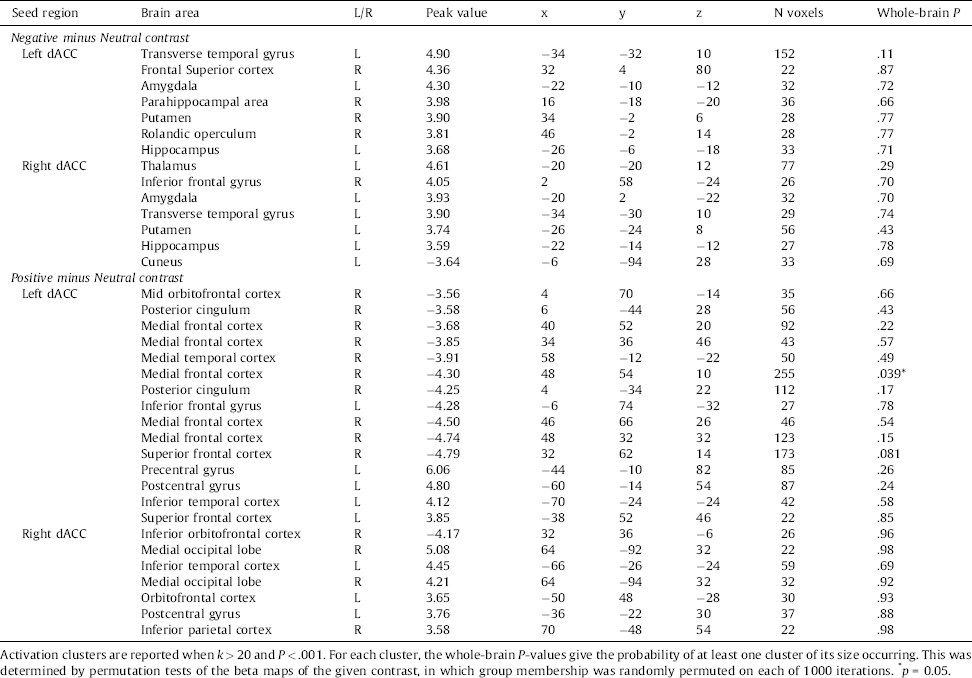

Table 5 Group differences in dACC coupling during negative versus neutral picture viewing.

PPI analyses using the left and right dACC as seed regions, revealed stronger connectivity with the amygdala in the Aggression group compared to the control group during the Negative minus Neutral contrast, using a threshold of P < .001, uncorrected. The Positive minus Neutral contrast revealed diminished connectivity with the (orbito)frontal cortex in the Aggression group. All differences are shown in Table 5.

Using the dACC as a seed region, differences in functional connectivity between the two groups were found. During the viewing of negative pictures, the Anger group show stronger connectivity between the left amygdala and both the left and right dACC. This is similar to a previous finding in which participants with an anxiety disorder showed increased dACC-amygdala connectivity during the viewing of negative facial stimuli Reference Robinson, Krimsky, Lieberman, Allen, Vytal and Grillon[45]. Because the dACC is involved with responses to stimuli requiring control or adaptation Reference Bush, Luu and Posner[46], this effect might indicate a tendency to attend to negative stimuli and respond to them via up-regulation of their emotional processing Reference Robinson, Krimsky, Lieberman, Allen, Vytal and Grillon[45]. Furthermore, the diminished connectivity of the dACC with frontal areas as observed in the Aggression group, might point towards reduced attention to positive stimuli or their evaluation Reference Etkin, Egner and Kalisch[23, Reference Kanske, Heissler, Schönfelder, Bongers and Wessa47]. The hemispheric effect is hard to interpret, however, a systematic review reported that the left amygdala often shows stronger activation compared to the right amygdala Reference Baas, Aleman and Kahn[48]. Taken together, the connectivity results therefore suggest a negative bias in attentional processes that could skew the perception of situations as threatening. We note however that these results were not generally whole-brain significant. Future studies need to confirm the valildy of our findings and interpretations.